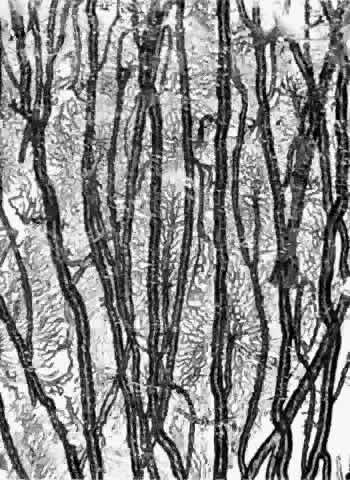

Torczynski and Tso27 reported on the architecture of the choriocapillaris in the posterior pole after examining choroidal flat preparations and transverse and oblique histologic sections (Figs. 21, 22, and 23). They described the overall appearance of the posterior choriocapillaris as a series of adjoining lobules that was striking in some preparations and subtle in others. The center of the lobule consisted of a single precapillary arteriole rimmed in a thick mantle of collagen measuring 15 to 25 μm and opening perpendicularly or curvilinearly into a capillary bed that radiated an average distance of 300 to 400 μm before changing from a radial to a circumferential direction. The circumferential capillaries in the periphery of the lobule were wider and converged from several directions, forming star-like or dendritiform configurations in the plane of the choriocapillaris. Venular openings, outward bulgings of the external choriocapillaris called atria, measured 30 to 37.5 μm and were present singly and in linear sequences underlying the circumferential capillaries. The often incomplete lobules varied in their geometric configuration, having three to six sides and ranging in area from 420 × 605 μm to 800 × 1200 μm. The lobular unit was thought to provide a preferred outflow route via the perimeter of postcapillary venules so that cross-flow from lobule to lobule would not normally occur, and thus the precapillary arteriole would function as an end-arteriole.

Fig. 21. Flat preparation of choriocapillaris, posterior pole. A. Arrowheads indicate oval openings to the postcapillary venules. The area around the precapillary arteriole (white-bordered arrow) is stained more heavily because of residual subcapillary collagen. (PAS, × 180; AFIP Neg 74-9984) B. Postcapillary venules (arrowheads) form an irregular ring bordering the capillaries that radiate from the precapillary arteriole (white-bordered arrows), thus outlining a single lobule. The capillaries are broader and clearer near the venules because of less subcapillary collagen. (PAS, × 100, AFIP Neg 74-10240) C. The openings of the postcapillary venules (as shown above) are connected with black lines; they demarcate adjoining lobules in the choriocapillaris. Capillaries from adjoining lobules enter the intervening venules. The lobules form a mosaic of adjoining vascular beds. Precapillary arterioles are indicated by white-bordered arrows. (PAS × 55; AFIP Neg 74-9985)

Fig. 23. Prominent lobular pattern in choriocapillaris with venules (arrowheads) surrounding arterioles (arrows). (AFIP Neg 75-3895; PAS, × 55) (Torczynski E, Tso M: The architecture of the choriocapillaris at the posterior pole. Am J Ophthalmol 81:428, 1976)